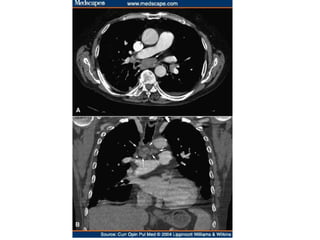

Arco Aórtico a Direita

www.szote.u-szeged.hu/radio/erek/aperi10c.htm